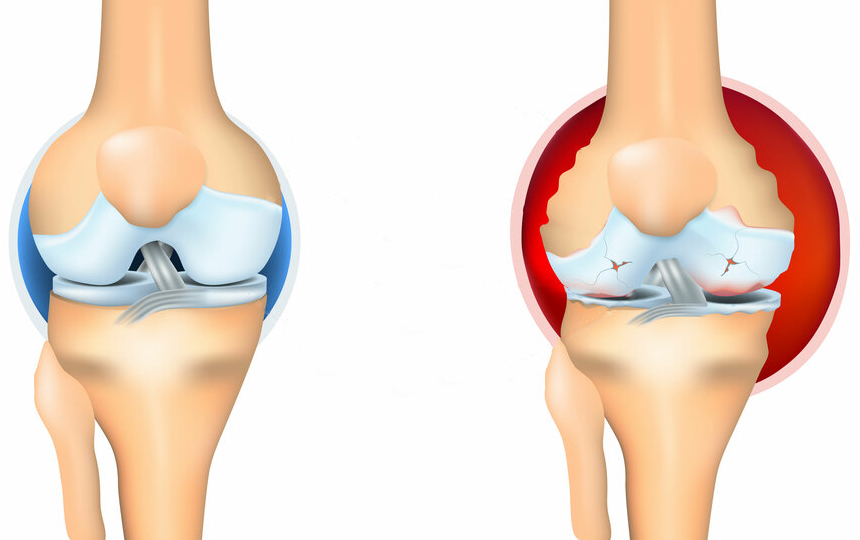

พวกนี้ไม่ช่วยเสริมสร้างข้อต่อหรือกระดูกอ่อนเลย พวกมันเพียงแค่ลดอาการชั่วคราว เช่น ปวด บวม อักเสบ ลองนึกดูว่าร่างกายจะเป็นอย่างไร เมื่อคนเรากินยา ทายาชา หรือฉีดยา ความเจ็บปวดก็จะหายไปชั่วคราว แต่เมื่อยาฤทธิ์หมด ความเจ็บปวดก็จะกลับมาอีก

อาการปวดเป็นสัญญาณสำคัญที่บ่งชี้ว่ามีความผิดปกติในข้อ การแค่ทำให้หายปวดจะทำให้สภาพของข้อต่อแย่ลง กระบวนการเสื่อมสภาพจะเร็วขึ้น 3-5 เท่า ส่งผลให้เกิดการเปลี่ยนแปลงที่ย้อนกลับไม่ได้ สูญเสียการเคลื่อนไหวและนำไปสู่การพิการในที่สุด

เมื่อเกลือเหล่านี้เกาะอยู่บนพื้นผิวของข้อต่อ คราบเกลือเหล่านี้เหมือนกระดาษทรายที่ทำลายเนื้อเยื่อรอบโดยรอบ กระดูก และกระดูกอ่อน เมื่อผลึกโตขึ้น เกลือจะเริ่มทำลายเนื้อเยื่อของกล้ามเนื้อ เอ็น หลอดเลือด และเส้นเลือดฝอย ทำให้เกิดการอักเสบ ติดเชื้อ บวม ก่อให้เกิดการอักเสบและปวดอย่างรุนแรง

ในกรณีรุนแรง การสะสมเกลือจำนวนมากอาจทำให้กระดูกหักได้ง่ายเมื่อมีการเคลื่อนไหวอย่างกะทันหัน ส่งผลให้พิการและข้อต่อไม่สามารถเคลื่อนไหวได้